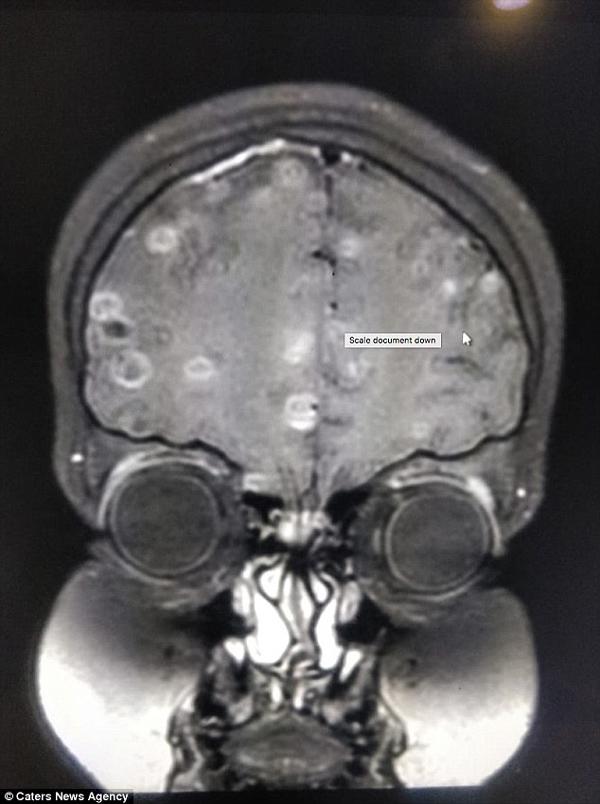

Sau 6 tháng chữa trị mà không có chuyển biến, cha mẹ cô bé rất lo lắng nên đã đưa cô đến Bệnh viện Fortis ở Gurgaon. Sau khi chụp chiếu và kiểm tra kỹ lượng, các bác sĩ rất bất ngờ khi phát hiện có đến trăm quả trứng sán dây đang "yên vị" trong não của cô bé. Đó chính là nguyên nhân khiến em có dấu hiệu bị loạn thần kinh và co giật.

Praveen Gupta, giám đốc thần kinh tại Bệnh viện Fortis, cho biết: “Việc chụp cắt lớp não của cô bé đã thấy hơn 100 chấm trắng hình thành do trứng của sán dây. Nguyên nhân là do ăn phải thực phẩm có chứa trứng sán.